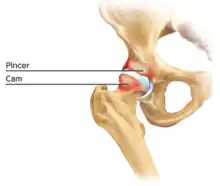

Figure 6. Diagram of the bony pathology of both cam and pincer impingement

Femoroacetabular impingement (see fig. 6)

Cam impingement is created by the abnormal development of the femoral head-neck junction causing what has previously been described as a 'pistol-grip deformity'. This type of deformity is characterised by varying amounts of abnormal bone on the anterior and superior femoral neck at the head-neck junction (see fig. 6). The head-neck junction is at the base of the ball of the hip, where it joins the short neck, which in turn carries on downwards into the femur, or thighbone, itself. A bony protrusion or bump at the head-neck junction has been likened to a cam, an eccentric part of a rotating device. This leads to joint damage as a result of the non-spherical femoral head being forced into the acetabulum mainly with flexion and/or internal rotation. This may impart compression and shear forces to the articular cartilage, and may lead to labral tears and peeling away of the articular cartilage from the underlying bone, so-called cartilage delamination (see fig. 8).[9][10]

Pincer-type femoroacetabular impingement

In contrast, pincer impingement is a result of an abnormality on the acetabular side of the hip joint.[2] The acetabulum may either have a more posterior orientation than normal, otherwise known as acetabular retroversion (seen as the crossover sign on AP radiographs), or there may be extra bone around the rim. This results in contact of the femoral neck against the labrum and rim of the acetabulum during hip movement earlier than might otherwise be the case. Repeated contact between the femoral neck and the edge of the acetabulum may lead to damage to the labrum and adjacent articular cartilage. Bone formation, or ossification within the labrum may be commonly seen as a result of this repeated contact. It is thought that this type of impingement may also predispose to the development of osteoarthritis.

The goal of the arthroscopic treatment of pincer impingement is to reduce the acetabular over coverage of the hip. Methods to reduce this over coverage of the ball by the socket include labral detachment or peel back, acetabular rim trimming using burrs, often reattaching the labrum with anchors at the end of the procedure. With the exception of cases of severe global over coverage of the hip, or situations in which the existing labrum has turned to bone (or ossified), excessive acetabular rim resection should be avoided in order to prevent iatrogenic increases in hip joint contact pressures.[14]